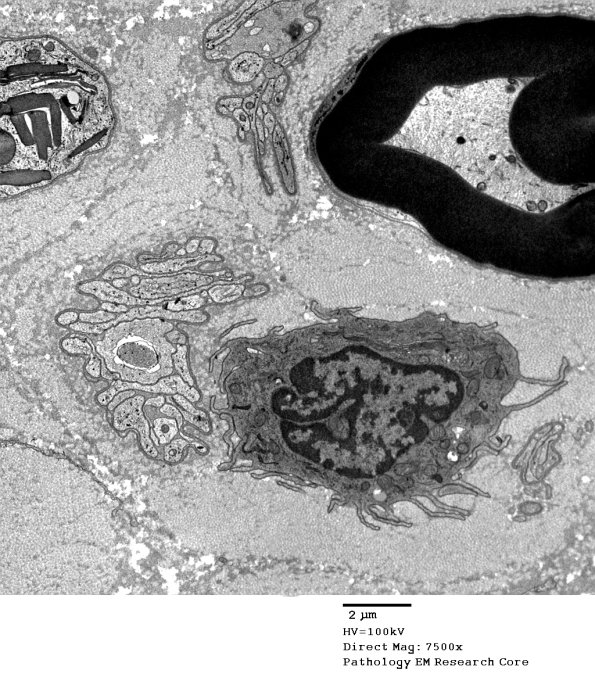

Washington University Experience | PERIPHERAL NEUROPATHY | 4 AXONAL DEGENERATION | 4 Macrophages | 1B4 Axonal Degeneration Macrophage (Case 2) EM 061 - Copy

These macrophages, again lacking engulfed material, are located in a nerve fascicle which has lost most of its axons. Note the empty Schwann cell processes forming bands of Büngner